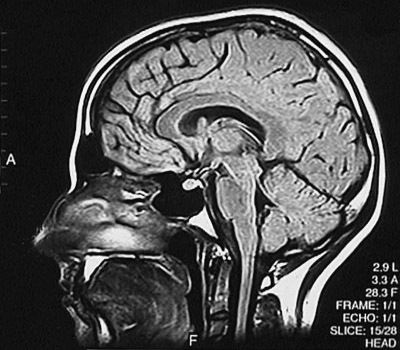

This is a normal sagittal FLAIR MRI scan demonstrating the midline with the frontal lobe and parietal lobe and occipital lobe and cerebellum and genu of corpus callosum and splenium of corpus callosum and mammillary body and thalmus and midbrain and pons and medulla and cervical spinal cord and tongue and nasal cavity.